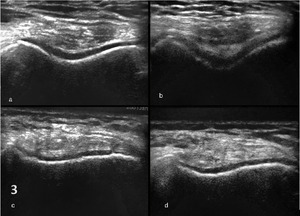

Diagnosis: Early and accurate diagnosis of trochlear dysplasia, cartilage wear, subchondral bone changes, or maltracking can lead to timely and targeted interventions. (Figure 3)

-